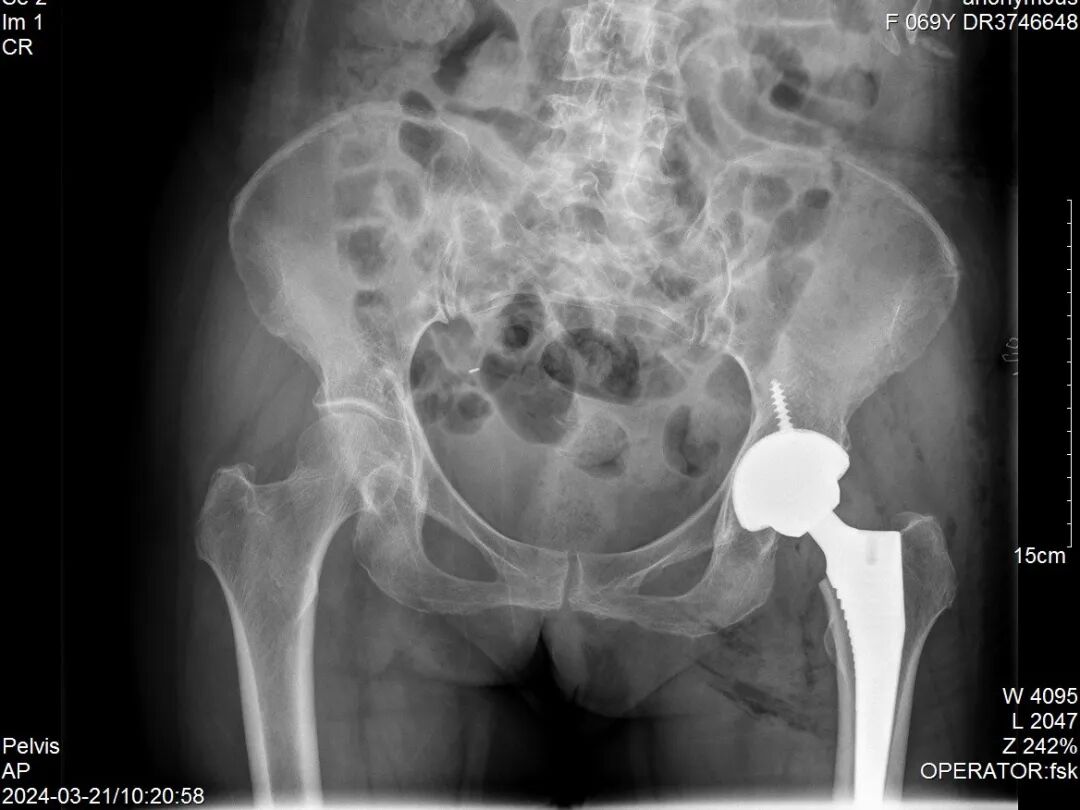

目前,VTS系统应用广泛,支持多种手术入路,在简单初次髋关节置换中,VTS系统精准辅助磨削让患者可以保留更多骨质,提高患者手术质量。在复杂髋关节置换中,VTS从规划到可视化假体植入再到可视化植钉追踪,全流程辅助提高了手术的安全性,让医生胸有成竹。

Visual Treatment Solution™(简称:VTS)是凭借医工交互进行术前规划与可视化实时监控的解决方案,旨在提升全髋关节置换术的手术性能和临床疗效。该系统将3D打印数字化制造技术与可视化智能辅助技术相结合,适应髋关节置换术中复杂的工作环境,从术前CT数据处理、3D手术规划,到术中的实时可视化追踪及髋臼假体植入等全流程进行辅助。